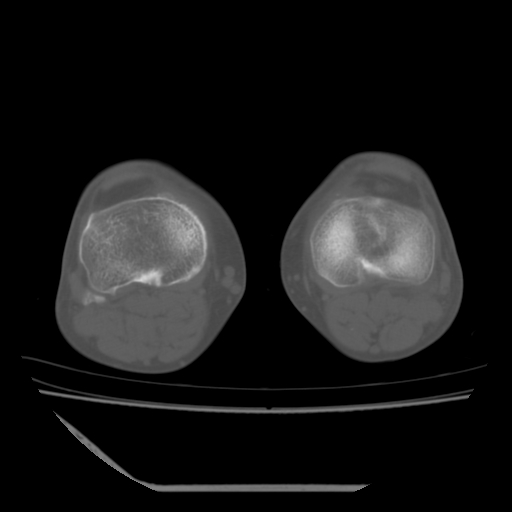

标题: CT13225:老年男性,左膝关节疼痛数月;请各位老师讨论。 [打印本页]

标题: CT13225:老年男性,左膝关节疼痛数月;请各位老师讨论。

骨质增生,骨性关节面硬化,关节积液,考虑退行性骨关节病

关节腔内少量积液,关节面退变。

双膝退变

骨质增生,骨性关节面硬化,关节间隙失常,关节积液,考虑退行性骨关节病.

这个病例诊断:退行性骨关节炎